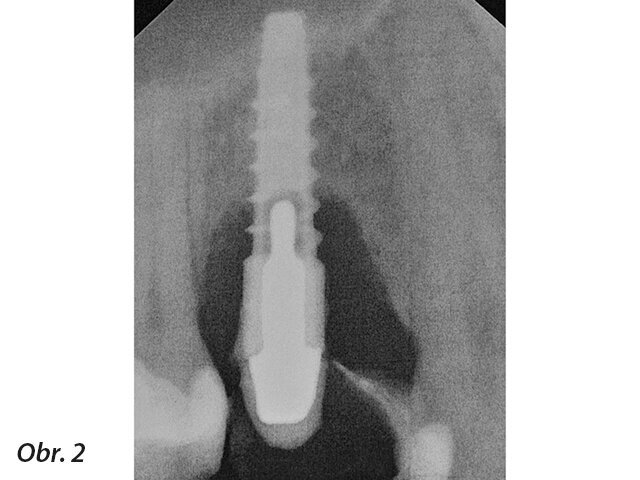

Intraorální rentgenový snímek téhož implantátu